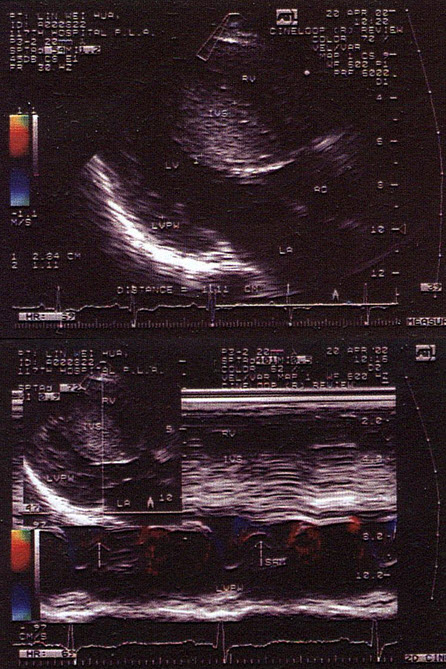

6、单项选择题

该病例最有可能诊断是()

A.左房黏液瘤

B.左房巨大血栓

C.左房恶性肿瘤

D.左房转移瘤

E.以上都不是